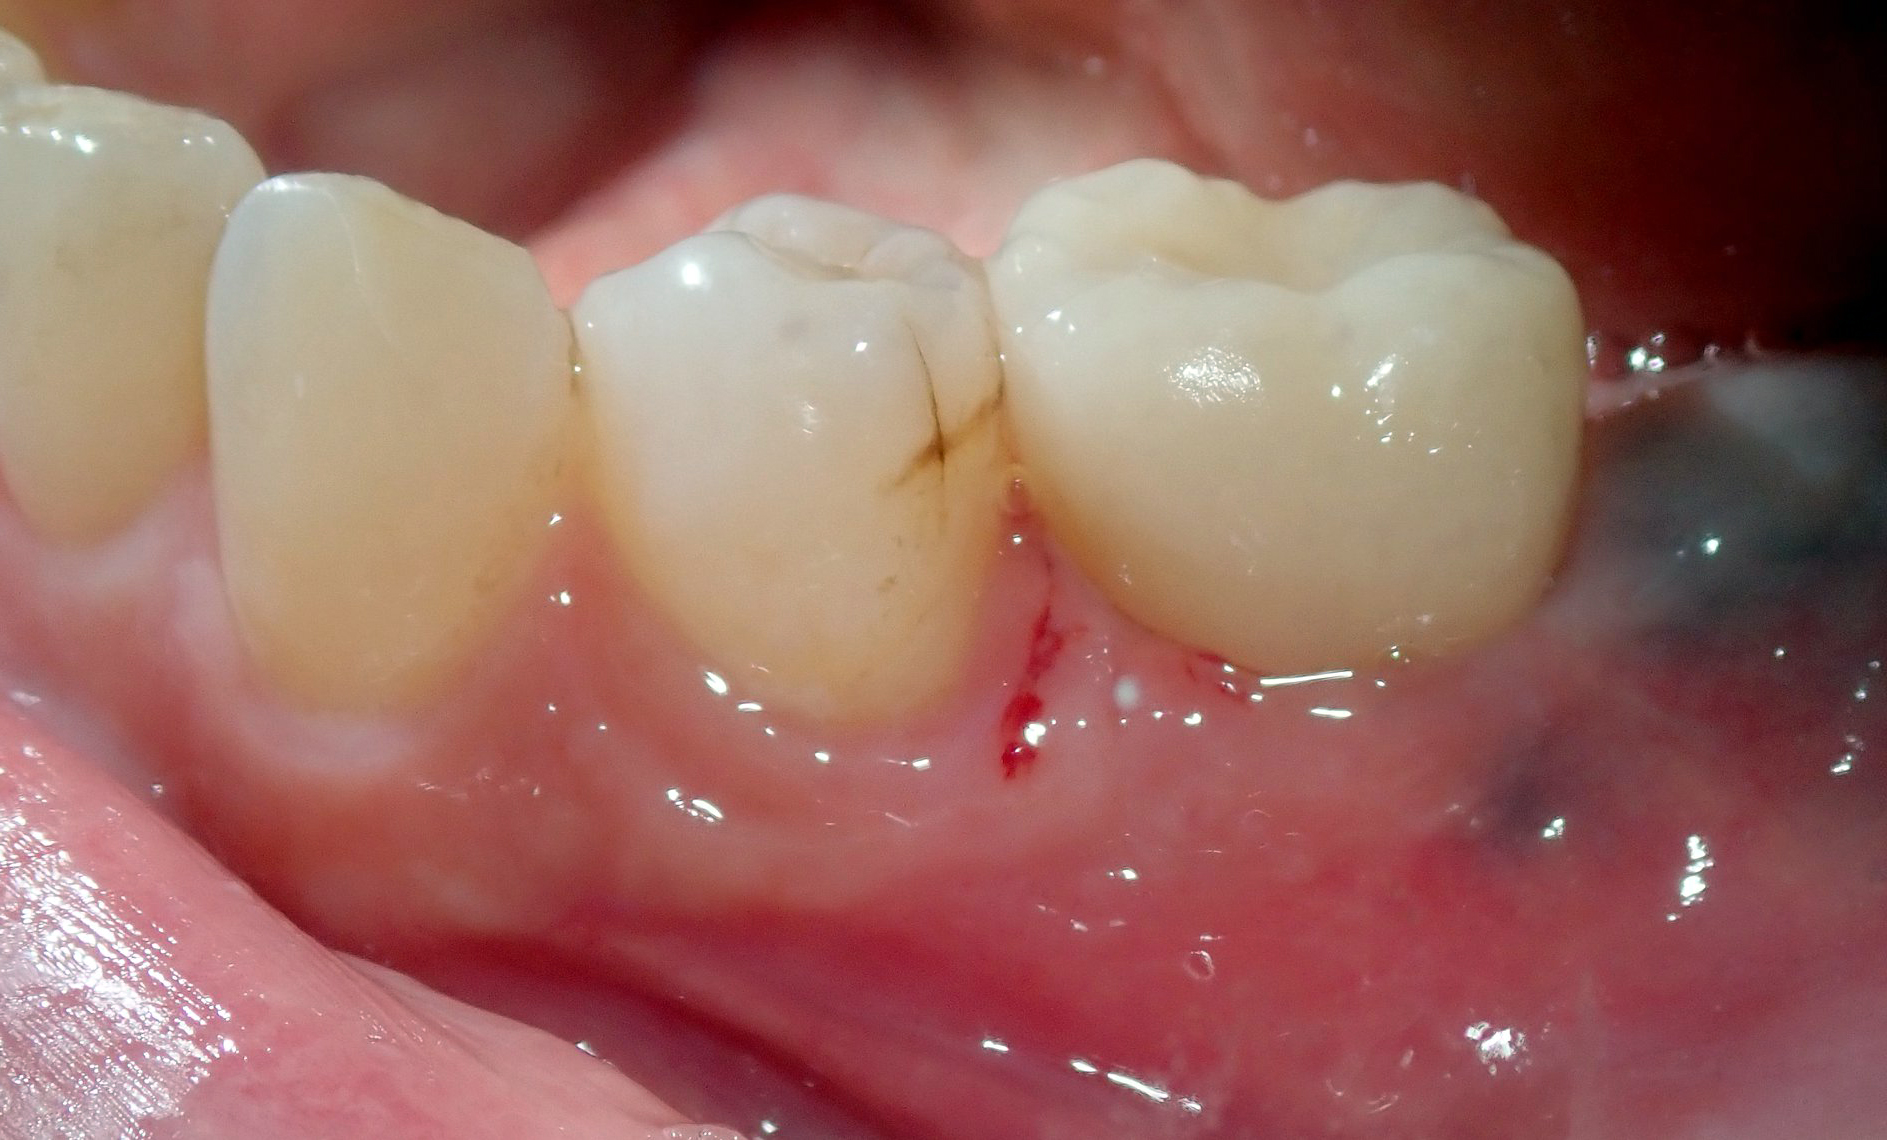

Fig 15. After healing, the gingiva around the emergence custom healing abutment was ready for initiation of the restorative phase of treatment.

Figure 15

Fig 16. A natural emergence profile for a mandibular molar, square in cross-section, was developed as evidenced upon removal of the custom healing abutment.

Figure 16